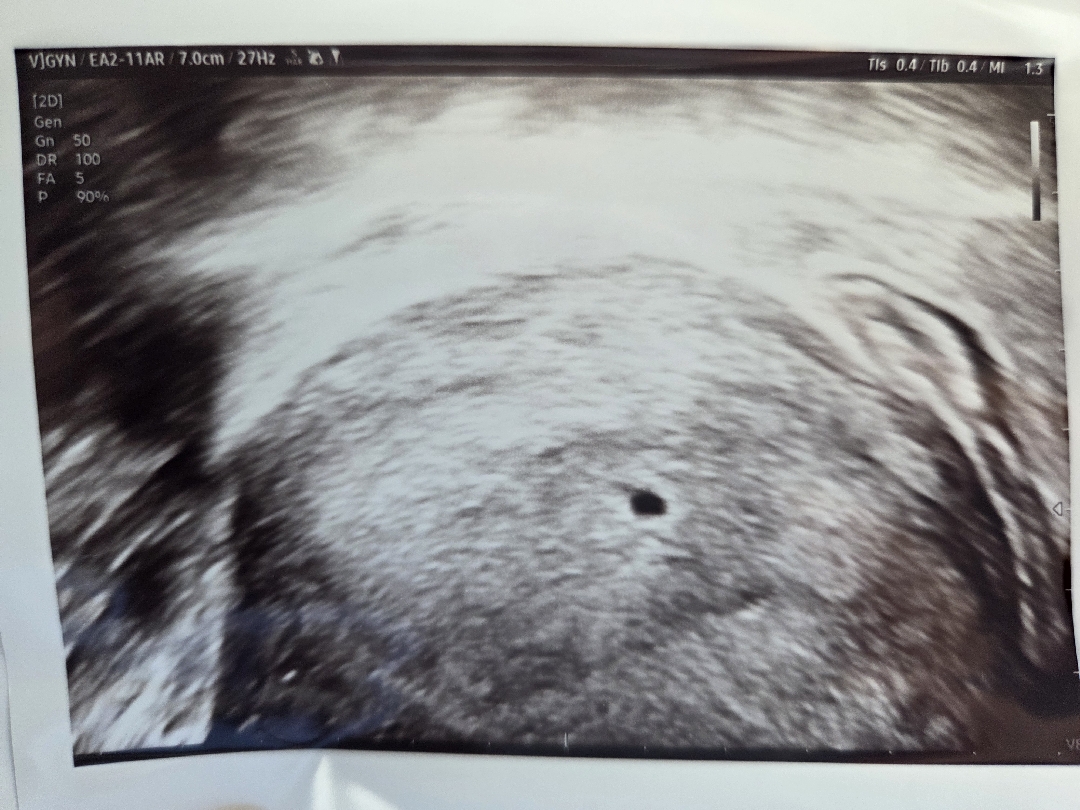

4주6일차 초음파 보고왔어요-!

다행히 위치도 좋고 자궁내막 두께도 괜찮다고 하셔서 조금 마음이 놓이는데 집이 너무 작은것같아요😭 10일 정도 뒤에 심장소리 들으러 오라고 하셨는데 오늘 배뭉침도 심하고 찌르듯이 아픈데 괜찮은거겠죠..??